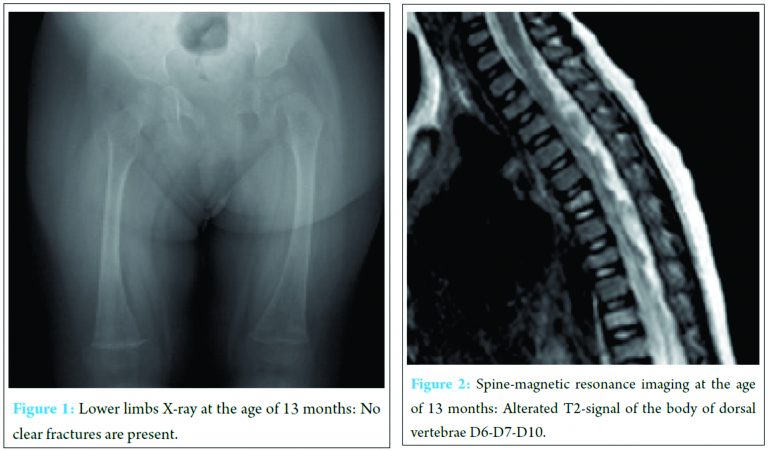

The patient was born by cesarean section with polyhydramnios at the 39th week of gestation with a birth weight of 2800 g, length of 48 cm, and head circumference of 35 cm. No perinatal problems were reported, and APGAR scores were 9 and 10 at 1 and 5 min, respectively. The development milestones were delayed, and the child had difficulty in maintaining a sitting position at the age of 7 months and in holding a standing position at 14 months. At admission, the girl weighed 8 kg with a height of 70 cm and head circumference of 44 cm (all in the third percentile). No malformative anomalies were evident, and no blue sclerae were observed. She interacted well with her parents and other people and showed good cognitive development. Arm and hand movements were possible, but she showed marked motor delay, particularly in the lower body. The patellar tendon reflexes, muscle strength, upper limbs function, and truncal control were not involved. The heart and respiratory system were normal as were the liver and spleen. Routine laboratory analysis was normal, including hemogram, coagulation testing, blood lactate, pyruvate, glucose and ketones, CK, copper and ceruloplasmine, plasma and urine amino acids, and urinary organic acid. Serum calcium levels were slightly elevated: 10.8 mg/dl (n.v. 8.8-10.6); phosphate: 5.0 mg/dl (n.v. 2.5-4.5). Electrocardiography, echocardiogram, wake and sleep electroencephalography, and electromyogram were normal. No bone lesions were found in lower limb X-ray (Fig. 1). Brain magnetic resonance imaging (MRI) was normal, and spine MRI showed signal alterations in dorsal vertebrae bodies D6, D7, and D10 (Fig. 2). The lower limb hypotonia persisted without a diagnosis, and physiotherapeutic treatment was initiated, which resulted in a slight improvement. At the age of 19 months, the parents opted for other medical consultations, in which a new spine MRI revealed a major involvement of the previously lesions in vertebral bodies D6-D7 and D10 with new vertebral involvements localized in the L2-L3 lumbar vertebrae. At the age between 22 and 25 months, the little girl showed various mild trauma fractures, the first localized on the right ulna, and subsequently, on the right tibia and fibula with early healing. We observed her again at the age of 28 months. The clear evidence of blue sclerae along with the easy fractures led us to the diagnosis of OI. The molecular analysis mutation of the COLI A1 gene displayed the germinal deletion c.52delC (p.